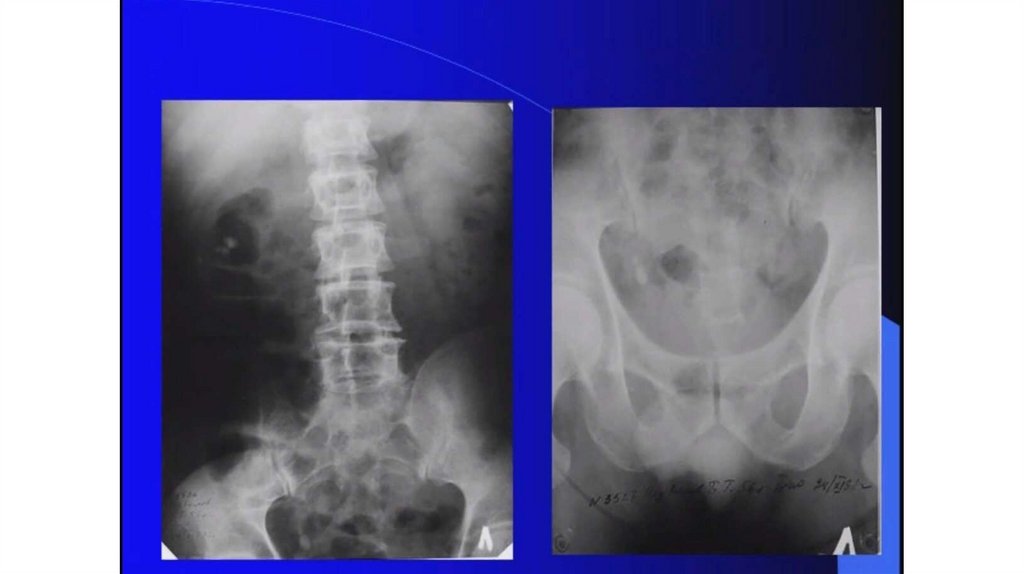

Мочекаменная болезнь. Мочекаменная болезнь и беременность

Мочекаменная болезнь